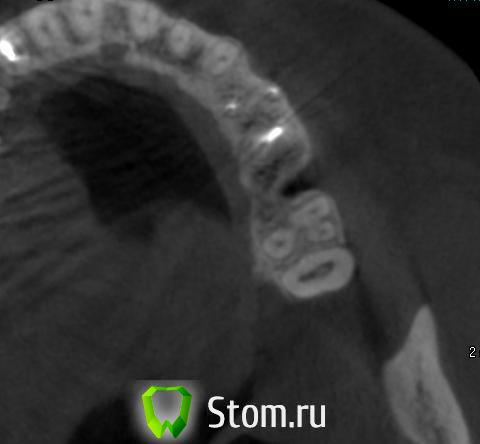

doktorenok Опубликовано 5 декабря, 2011 Поделиться Опубликовано 5 декабря, 2011 Вот чисто теоретически Возможна ли здесь имплантация? Если да, то какова последовательность действий по пластике? Зуб удален год назад, соустье ушито, жалоб никаких не было. Ссылка на комментарий